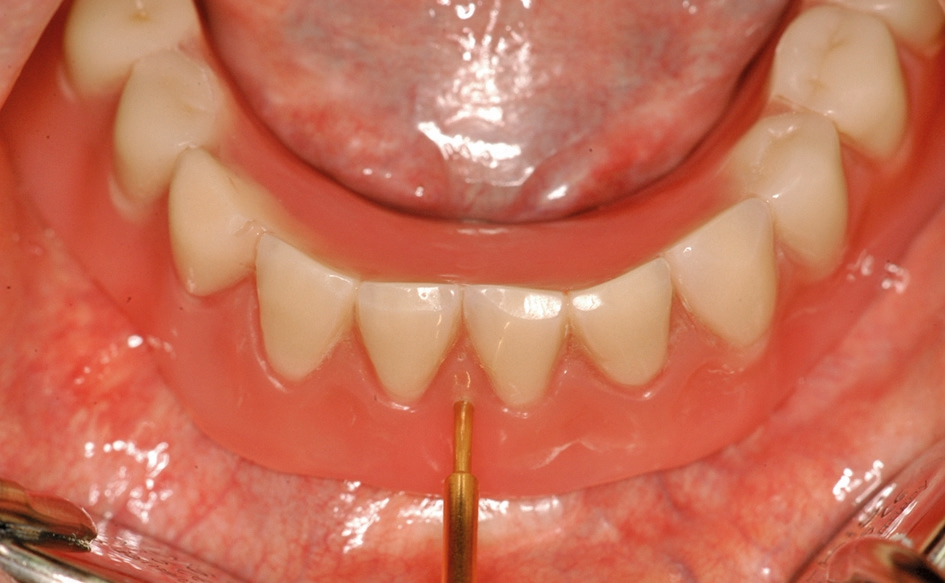

Abb. 1: Ein ausreichend dimensionierter, breiter Kieferkamm ist vorteilhaft für die Behandlung.